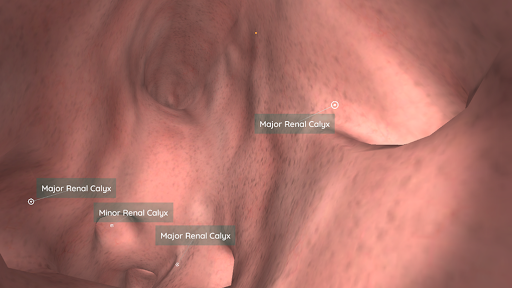

Korzystając z wirtualnej rzeczywistości, będziesz w stanie poruszać się wzdłuż struktur anatomicznych, stając się częścią ludzkiej anatomii: układu rozrodczego układu krążenia, oddechowego, trawiennego, moczowego, łzowego i żeńskiego.

W trybie wirtualnej rzeczywistości urządzenie mobilne (smartfon) musi być umieszczone w gadżecie wirtualnej rzeczywistości, aby cieszyć się w pełni wciągającym doświadczeniem. Użytkownik może wchodzić w interakcję z elementami sterującymi nawigacją i elementami informacji anatomicznej, kierując je na cel.

To nowo odnowiona wersja Anatomyou VR. Dodatki zawarte: - Bardziej realistyczna anatomia człowieka, ulepszająca modele i tekstury. - Lepsza interakcja użytkownika w VR i trybach pełnoekranowych. - Całkowicie odnowione menu i obrazy zapewniają intuicyjną nawigację. - Dodatkowa treść kliniczna potwierdzona przez naszych ekspertów. - Poprzedni użytkownicy muszą zaakceptować pewne uprawnienia (pakiet SDK GoogleVR). Włożyliśmy wiele wysiłku w to ulepszenie, mam nadzieję, że Ci się spodoba!